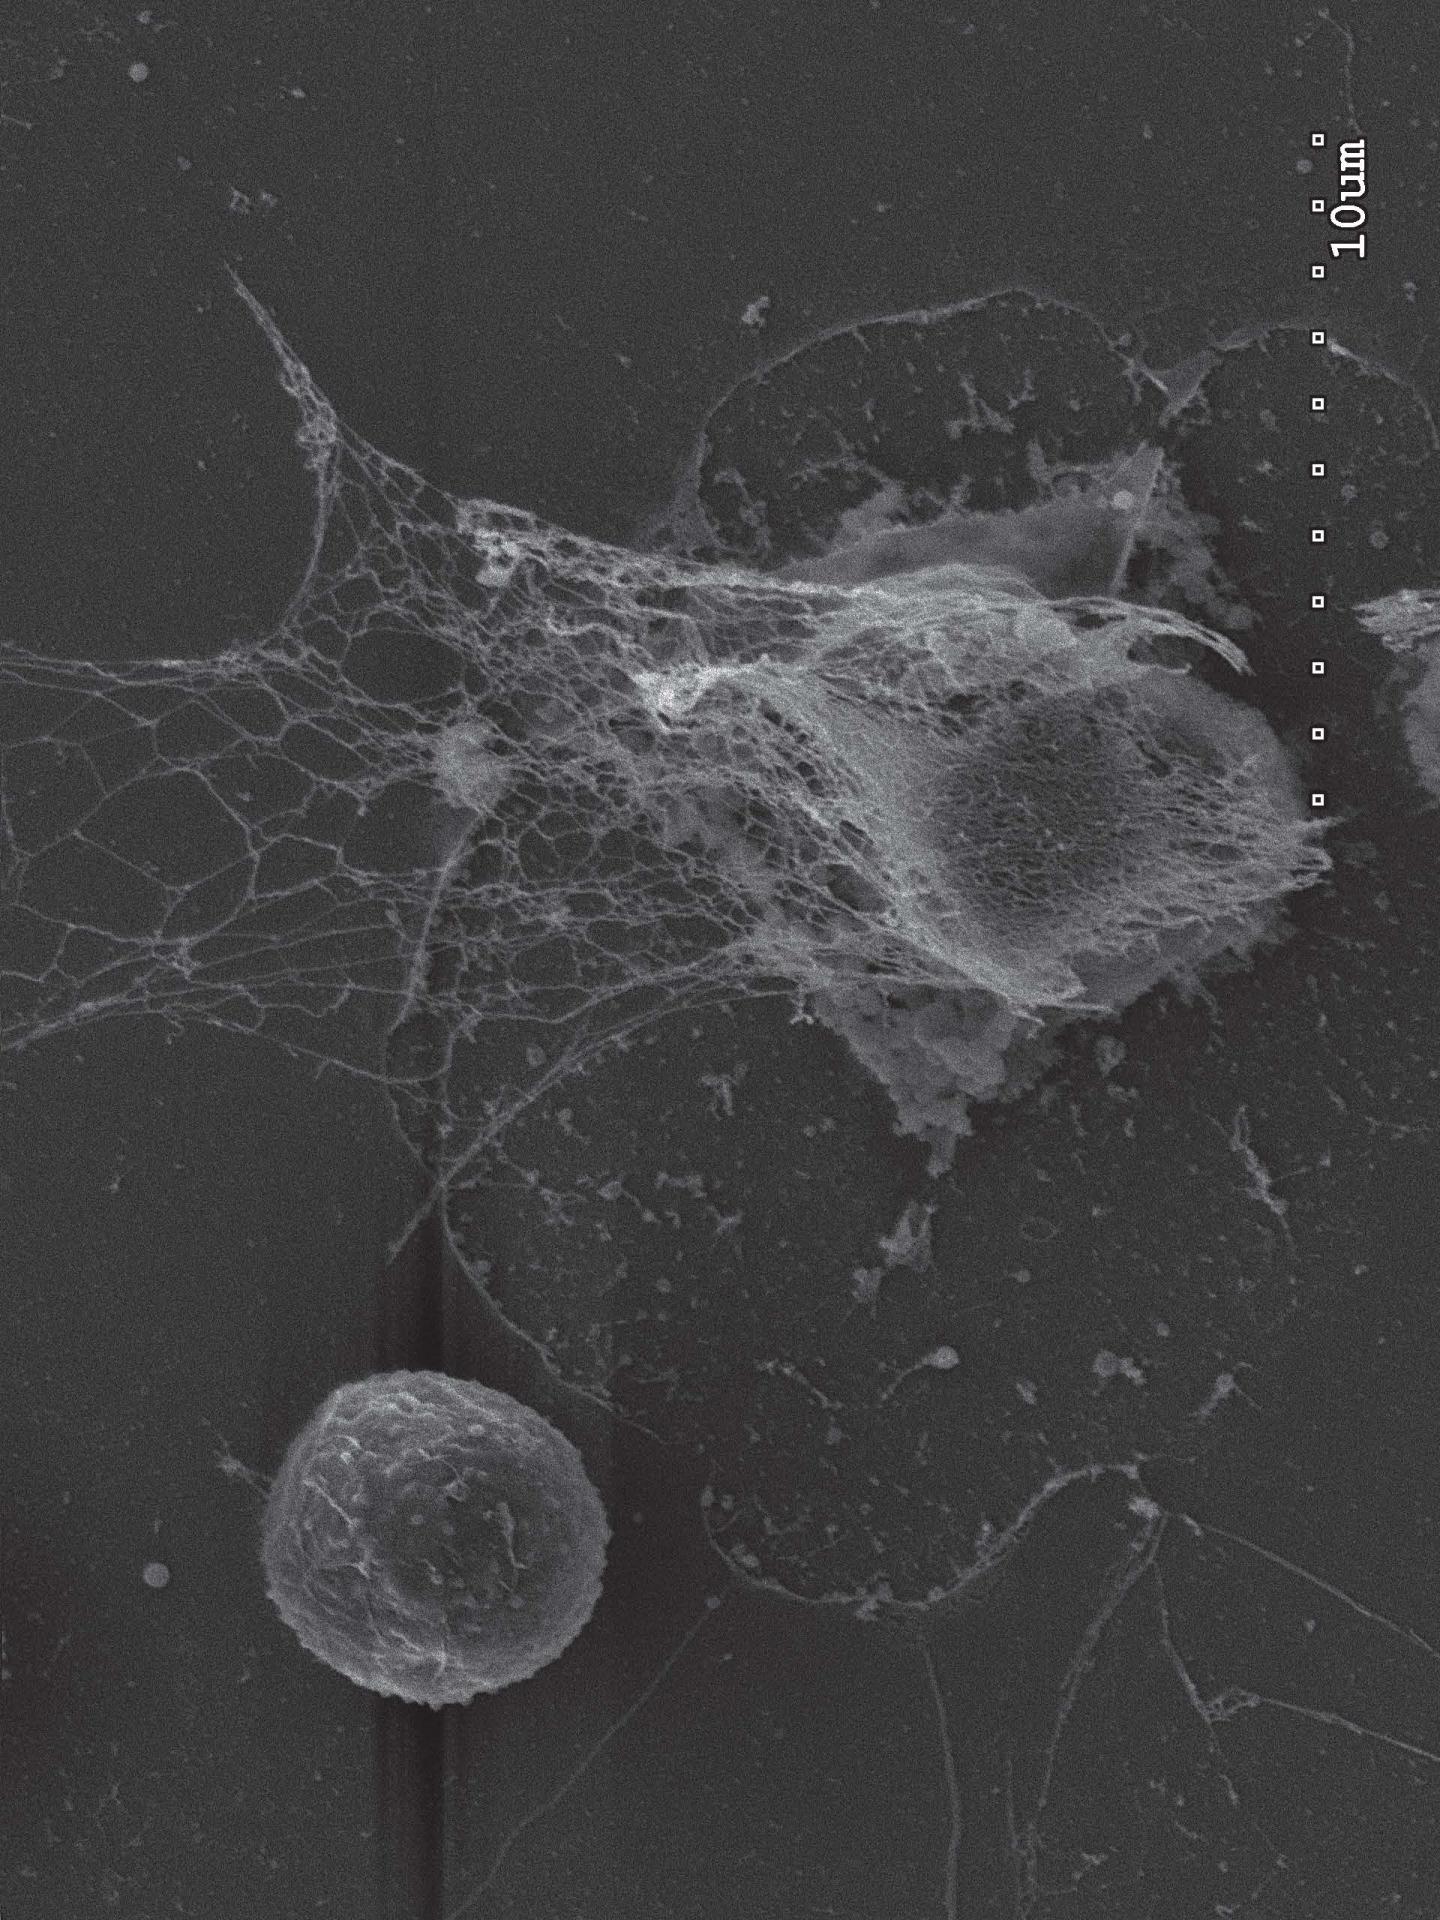

This astonishing weapon appropriated by cancer cells is a lattice of DNA, ejected from an activated neutrophil when the neutrophil detects a threat. Such nets -- appropriately dubbed neutrophil extracellular traps or NETs -- form dense spider web-like structures outside the neutrophil. The DNA that forms the backbone of the web is studded with tiny toxic enzymes that can degrade and digest invaders.

"The remarkable thing we witnessed in live imaging was the ability of cancer cells to induce nearby neutrophils to eject their NETs even when no infection or invader was present," says Egeblad. "Our experiments showed that the NETs, in such situations, can promote metastasis."

Although the precise mechanism is still being explored, Egeblad thinks NETs help cancer cells by literally eating through the proteins that form a tissue's scaffolding - thus opening up small holes and crevices that cancer cells can occupy. This can be a first step in forming a cancer colony at a site distant from the primary tumor.